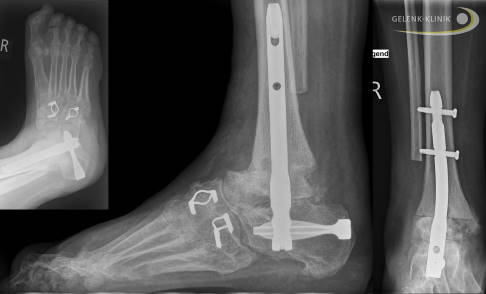

Operationen bei schweren Fußfehlstellungen

Schwere über Jahre entstandene Fehlstellungen oder Fußdeformierungen benötigen weitere korrigierende Operationen, die am Fersenbein oder auch an der Fußwurzel erfolgen können. Diese sind je nach Ausmaß zum Teil nur durch eine Versteifung mit Korrektur des Fußes realisierbar.

Eine Operation ohne Versteifung durch Verlagerung, Verdrehung oder Verkürzung am Fersenbein ist teilweise sinnvoll zur Veränderung der Stellung und der Fehlbelastung des Fußes.

Auch eine Stellungskorrektur am höchsten Punkt der Fehlstellung an der Fußwurzel kann eine sinnvolle Maßnahme sein. Diese Operation, bei der ein Fußkeil entfernt wird, ist gerade bei Fehlstellungen der Kleinzehen sehr effizient. Dabei wird ein Fußkeil aus dem Fußwurzelbereich entnommen und die Knochen danach wieder fixiert. Diese Korrektur ist neben vielen anderen Möglichkeiten eine sehr effektive Maßnahme, wenn nicht eine früher durchgeführte Behandlung die Fehlstellung verhindert. Je nach Ort der Fehlstellung kann die Position der Keilentnahme auch am 1. Mittelfußknochen im Rahmen einer sog. Tubby-Osteotomie oder am Fersenbein im Rahmen einer Calcaneusosteotomie oder Dwyer-Osteotomie sinnvoll sein. Die Wahl des Eingriffes kann zum Teil erst im Rahmen der Operation selbst erfolgen.

Möglichkeiten bei bereits vorliegender Arthrose durch eine Fehlstellung

Korrektur wenn kein Gelenkerhalt mehr möglich ist

Vorgehen bei den beiden Operationen

Primär ist die schwere Fehlstellung im Sprunggelenk und damit die Fehlstellung des Rückfußes zu behandeln.

Beim 2. Eingriff wurde dann die Fehlstellung der Fußwurzel durch eine Keilresektion aus der Fußwurzel behoben. Die dadurch erreichte gerade Stellung des Fußes beim Stehen und Gehen ist hier besonders wichtig. Die Begradigung und damit die insgesamt bessere Belastung des noch vorhandenen Gelenkes im Fuß sind wichtige Ziele.